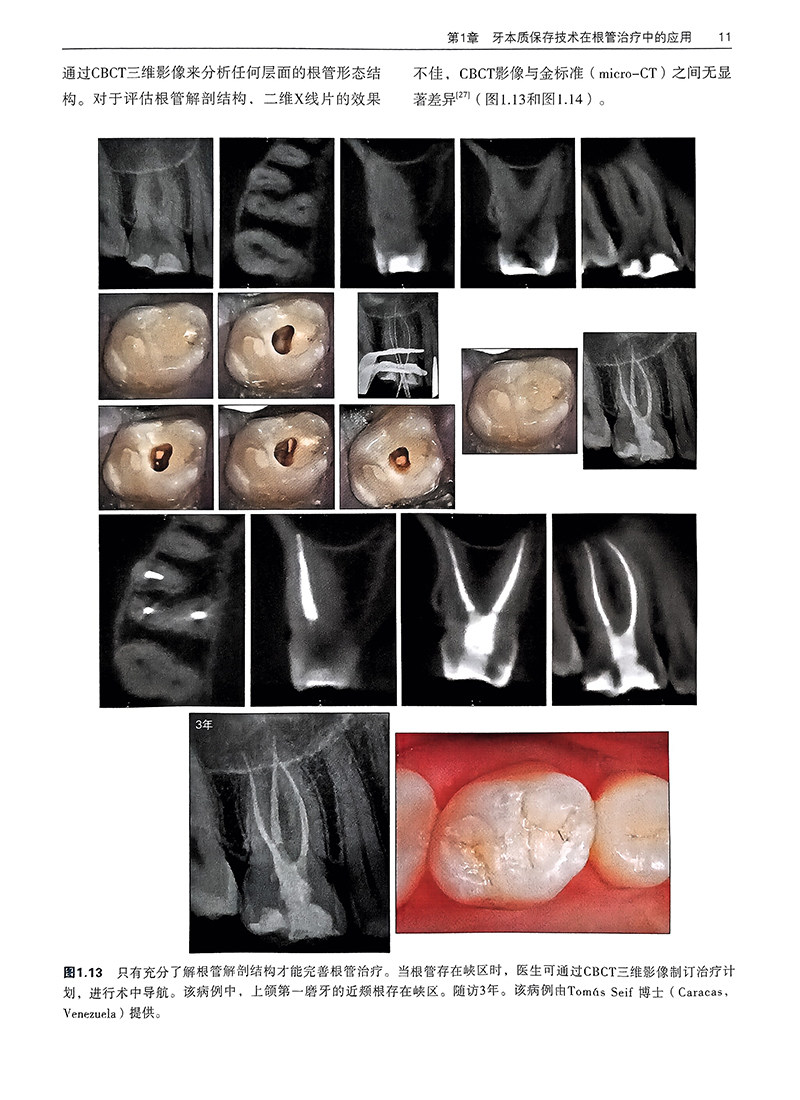

第1章 牙本质保存技术在根管治疗中的应用